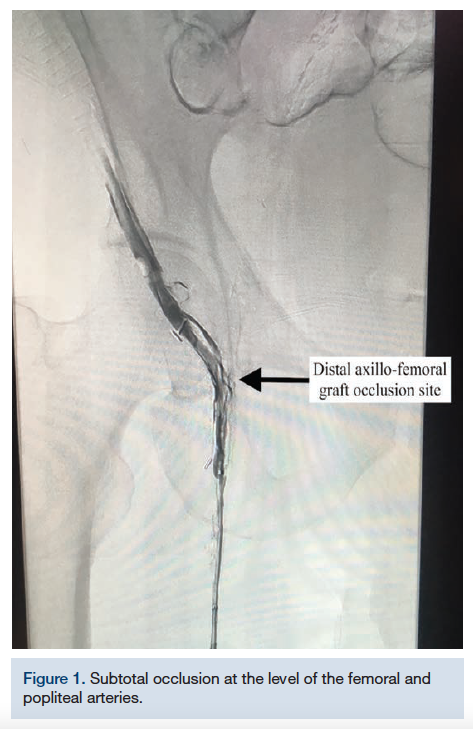

The right dorsalis pedis artery was accessed using ultrasound guidance and a 6 French (Fr) system was used. An .035-inch Quick-Cross catheter (Philips) was advanced from the transpedal access into the superficial femoral artery (SFA) for selective angiography, revealing the subtotal occlusion at the level of the femoral and popliteal arteries (Figure 1). The .035-inch wire and catheter were able to advance through the occlusion and into the axillary bypass graft. However, no equipment had the appropriate length to extend further into the axilla. The decision was made to proceed with transradial access to allow for both antegrade and retrograde approaches to revascularization. An .035-inch guidewire was positioned in the axillary bypass as a marker for locating the graft from the arm.